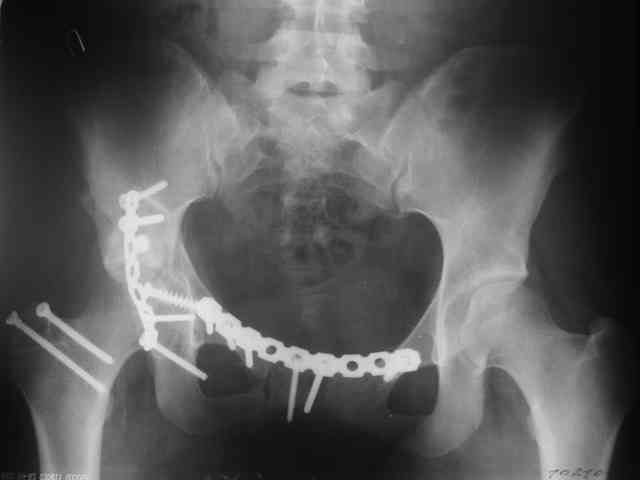

Трудности возникли сразу после рассечения большой ягодичной мыцы - короткие наружные ротаторы едва ли определялись - головка и шейка (как видно на

снимке) ушли в таз, пришлось воспользоваться дистрактором( ручные попытки выдернуть голову из под проксимального фрагмента - безуспешны) Шарнирный дистрактор - великое изобретение, без него репозиция была просто невозможна.

Дальше как обычно: рекон пластнина на заднюю колонну. Устранить смещение передней колонны из заднего доступа оказалось невозможным, пришлось

перевернуть больную на спину и из подвздошного доступа вернуть переднюю колонну на место. Другая проблема возникла с фиксацией лонной кости,

пришлось открывать ся над лобком и ретроградно двумя винтами фиксировать обе ветви лобковой кости справа и слева.

Пока всё ОК снимки сделали сегодня, но пока не сфотографировал В целом суставная поверхность конгруэнтна , по колоннам тоже вроде все ОК.

Интраопер под ЭОПом контролировал направление лонного винта - была абсолютная уверенность в правидльности направл, на постоп. снимке винт вылез :-((.